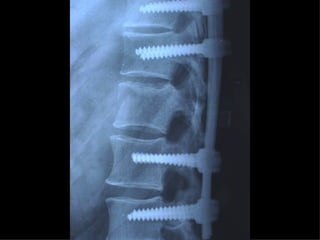

APPARATO LOCOMOTORE Hanno priorità assoluta  : Fratture esposte Fratture con lesioni vascolari e nervose Fasciotomie Fratture multiple delle ossa lunghe Fratture della colonna vertebrale

Fratture della colonna vetebrale

Tc pre op

Rx post

Timing chirurgico 1° GIORNO :- intervento salvavita - “Damage control” - trattamento chirurgico  primario differito 2°-3° GIORNO :  soltanto un “second  look”

5°-10° GIORNO :  “window of  opportunity”  per un intervento  definitivo 10°- 20° GIORNO : NESSUN TRATTAMENTO CHIRURGICO Dal 21° GIORNO : intervento chirurgico secondario - ricostruttivo